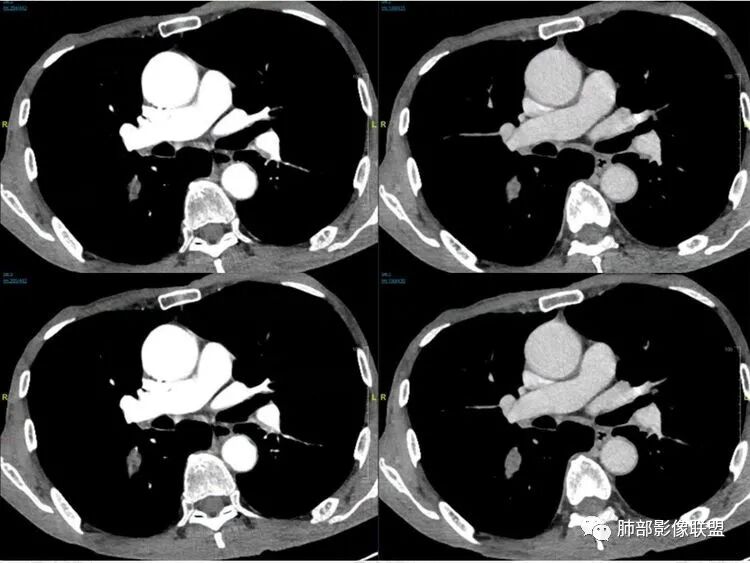

许慧良:

老年男性患者,胸部隐痛1月入院,有长期吸烟史,胸部CT:右肺下叶背段梭型结节灶,边界清晰,无明显分叶、毛刺及周边磨玻璃影,内部密度不均匀,支气管截断,增强扫描不均匀轻度强化,内部似乎见支气管黏液栓,纵隔淋巴结不大,考虑恶性病变:小细胞癌(缺少典型的纵隔肺门淋巴结增大融合),鳞癌(病史复合,但没有阻塞性肺炎,内部没有坏死,),类癌(多见于女性患者,与吸烟关系不大),首先考虑典型类癌,

飞鹰行动:

老年男性,右肺下叶梭形或椭圆形结节,形态较规则,边缘光整,支气管截断,增强不均匀轻度强化,右肺门及纵隔淋巴结增大,考虑恶性病变,鳞癌或小细胞癌,神经内分泌癌(小细胞形)。

红星:

老年男性患者,右肺下叶背段梭形结节影,边界比较光整,密度均匀,没有明显的分叶毛刺,没有阻塞性肺炎的表现,这些感觉具备有良性的特点。而近端支气管截断,增强明显的强化,纵隔多发的淋巴结,显得是恶性的特点。总体印象,老年患者+支气管截断征象+明显强化的结节+纵隔多发淋巴结,还是考虑恶性结节,小细胞癌或是鳞癌。

必有路:

男性,老年人,长期吸烟史,老慢支背景,右下肺背段占位,支气管亚段门口堵,病灶长轴与支气管平行,推测腔内生长可能,病灶内血管穿行,周围干净,轻度强化,右肺门淋巴结肿大,考虑恶性,神经内分泌癌(大小类)>淋巴上皮瘤样癌>腺癌>鳞癌

宇宙:

右肺下叶梭形实性结节,密度均匀,边缘光整,局部膨隆,近端支气管截断,轻度强化,血管走行自然,右肺门及纵隔淋巴结增大,考虑小细胞癌>鳞癌

王秀仙:

右肺下叶背段结节,沿着支气管走行呈长椭圆形,边缘圆滑清晰,近端支气管阻塞,远端支气管有沿壁增厚,右肺门淋巴结肿大,中度强化,老年男性,吸烟病史,肺气肿背景,考虑小细胞肺癌,鉴别鳞癌

丽:

老年男性,吸烟史,右肺下叶梭形肿块,边缘平直有分叶,支气管近端阻塞,右肺门肿大淋巴结,增强后轻度强化,欠均匀,首先考虑恶性,小细胞肺癌?

阳光:

老年男性+吸烟+右下肺肿块影+支气管截断+淋巴结肿大,考虑恶性,倾向小

小芳:

老年男性,吸烟史,右肺下叶背段梭型软组织肿块,边缘膨隆,不均匀强化,近端支气管截断,同侧肺门及纵隔淋巴结肿大,支持恶性,小细胞可能大,鳞癌缺少阻塞性改变

良孑:

晨读,右下叶梭形占位,边界光滑,支气管截断,可见尾征,不均匀轻度强化,肺门淋巴结肿大,有吸烟史,高龄高危患者,首先考虑恶性,考虑小细胞癌,鉴别一下鳞癌

傅昌瑜:

老年男性,前胸隐痛1月。2年前有白内障手术史。右下肺结节,沿中轴呈梭形,膨隆,边清、无分叶,无毛刺,近端支气管截断完全堵塞,病灶以远未见阻塞性炎症及肺不张。内部密度基本均匀,增强轻微强化,似见局部低密度影。纵隔及右肺门见肿大淋巴结。整体考虑恶性可能性大,小细胞癌?鳞癌?注意鉴别良性结节—错构瘤。

弹指之间:

老年男性,长期吸烟史,右肺下叶背段梭形低密度灶,边界清晰,无明显分叶、毛刺,边缘稍彭隆,支气管截断,右肺门淋巴结增大,增强扫描不均匀轻度强化(延迟略明显),首先考虑恶性,小?不典型结核球待排。

看图说话:

右肺下叶背段结节,气管堵塞,密度均匀,边界清晰,无明显分叶、毛刺,边缘膨隆,右肺门淋巴结增大,增强轻度强化,考虑小细胞癌,鉴别鳞癌。

自信人生:

右肺下叶梭形软组织结节,密度均匀,明显尾巴,边缘光整,近端支气管截断,轻度强化,血管走行自然,又腊肠尾巴征象

考虑恶性  小细胞癌?

流心明智:

男,83,前胸部隐痛不适1月。有长年大量吸烟史。胸部CT:肺气肿,右肺下叶纺锤型实性结节灶,边界清晰,支气管截断,内部密度不均匀,增强扫描不均匀强化,右肺门淋巴结大。考虑恶性病变:小?鳞?鉴别炎性肉芽肿、错构瘤等。

棉花糖:

晨读:老年男性+吸烟+右肺下叶与气管长轴一致的梭形肿块影+支气管截断,轻度强化,右肺门肿大淋巴结,考虑恶性,小细胞肺癌可能,鉴别鳞癌

南边:

有强化吗?

强化就支持恶性

呈典型管状改变,近端支气管堵塞、稍扩张,病灶有强化倾向于恶性,没有强化倾向于炎性病变(结核之类);近端呈结节状(鳞癌多一些),这个病例呈管状(小细胞Ca多一些);平扫与强化有差异,有轻度强化,是粘液栓还是血管?